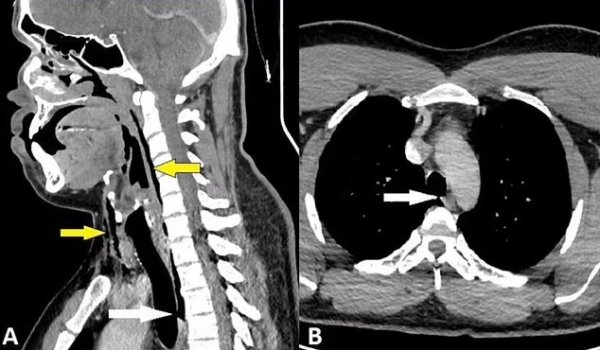

İskoçya’da inanılmaz bir olay yaşandı. Hapşırığını tutan bir kişi hastanelik oldu. İskoçya’da bir ilk yaşandı. Bir adam araba kullanırken hapşırığını bastırmaya çalıştı. Ardından acılar içinde kalan hasta, hastaneye gittiğinde nefes borusunda bir yırtık olduğunu öğrendi.